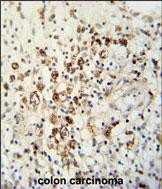

| IHC | 1/100-1/500 | Human,Mouse,Rat |

Antibodies against HAUS5 (N-term) are valuable tools for studying its expression, localization, and function in cell cycle regulation, particularly in cancer research, as HAUS5 dysregulation is linked to tumorigenesis. They are commonly used in techniques like Western blotting, immunofluorescence, and immunoprecipitation to investigate HAUS5's role in spindle dynamics, mitotic defects, or DNA damage responses. The N-terminal specificity ensures recognition of intact HAUS5. aiding in distinguishing it from degradation products or isoforms. Studies using this antibody may provide insights into diseases associated with mitotic errors, such as cancer or developmental disorders.